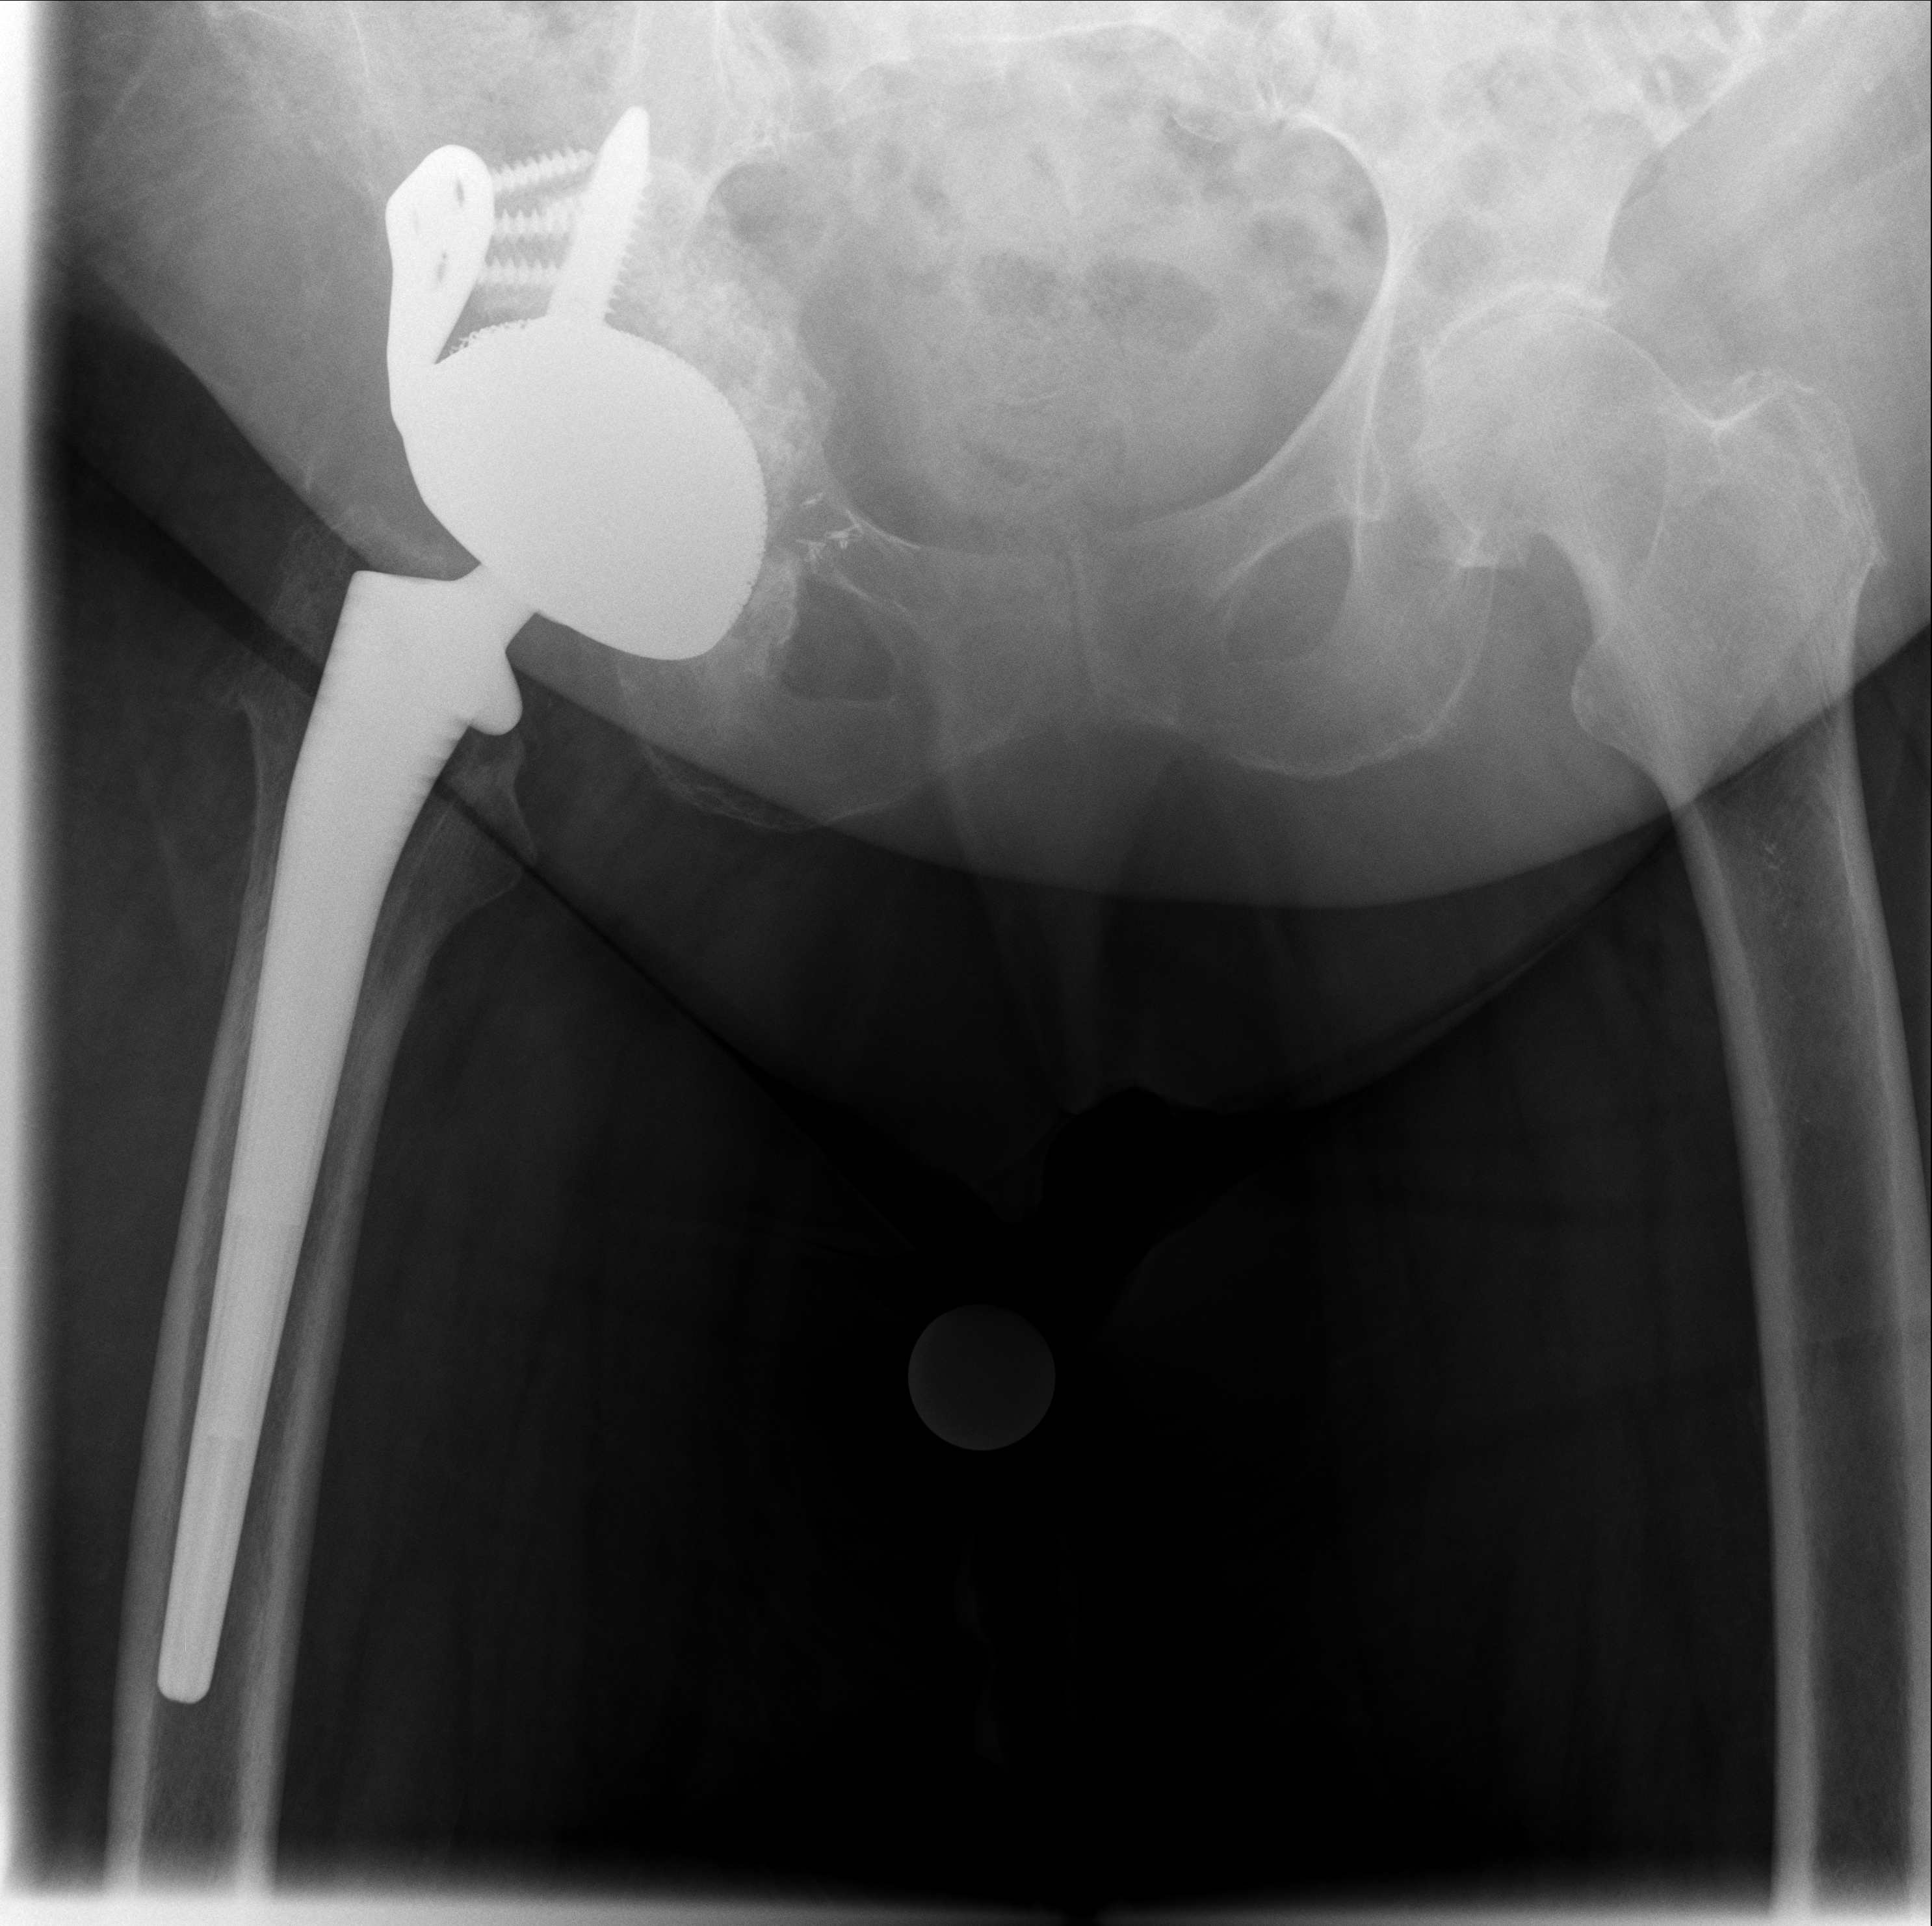

Bildvergleich: Behandlungsverlauf

Röntgenbilder im Verlauf: korrekte Lage → Luxation → neue TEP nach Wiedereinbau

24.02.2026 - Neue TEP

Röntgen Februar 2026

Neue Hüft-TEP rechts nach Wiedereinbau

24.02.2026 - Neue TEP!

Becken 2026

24.02.2026 - Postoperativ

Röntgen Becken + Hüfte rechts (Kontrolle nach Wiedereinbau)

3 Aufnahmen | Becken tief + 2x Hüfte Lauenstein | 5 Tage nach OP

Postoperative Röntgenkontrolle

Röntgen Becken tief + 2x Hüfte Lauenstein R – Kontrolle 5 Tage nach Wiedereinbau.